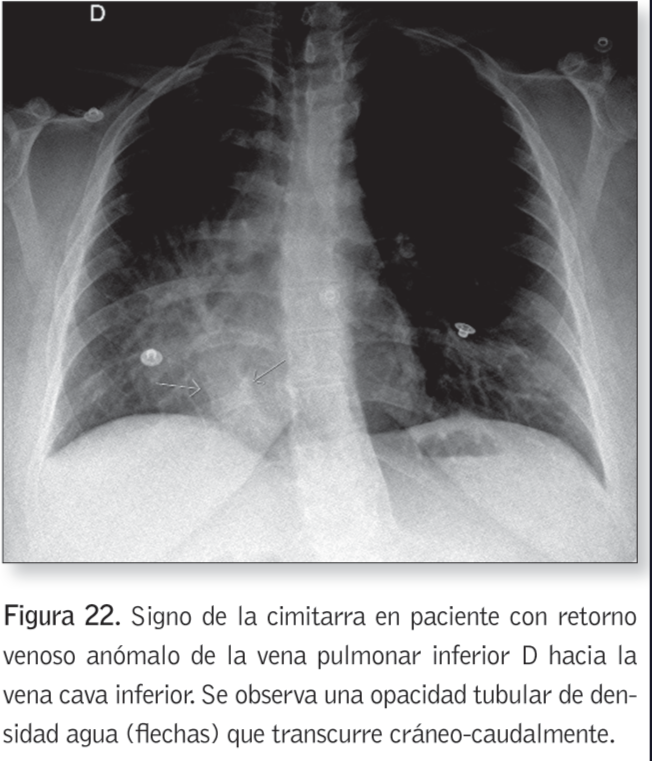

Signo de la Cimitarra

¿Cuándo se presenta el signo de la cimitarra?

En el Sx del pulmón hipogenico (retorno venoso anomal de la v. pulmonar a la hepática)